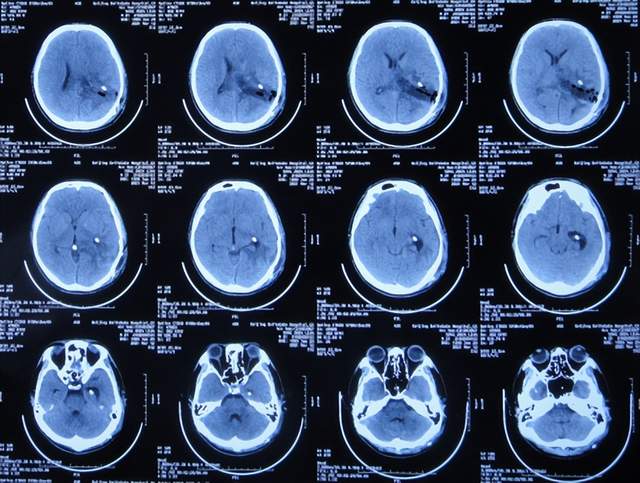

出院后5个月即2021年9月中旬,出现偶尔头痛的症状,因此于出院后7个月后即2021年11月10日,第2次来到李小勇脑脊液科;入院时:时有头痛(图-26),身体其他正常;查头颅CT示左侧颞角扩张(图-27)。

图-26:2021年11月10日入院时

图-27:入院时头颅CT

入院后2天即2021年11月12日,给予了颞角分流管调整术;术后第2天查头颅CT示颞角仍扩张(图-28)。

图-28:2021年11月14日头颅CT

入院治疗14天即2021年11月24日,查头颅CT示颞角缩小(图-29),患者头痛基本消失(图-30)。

图-29:2021年11月24日头颅CT

图-30:2021年11月24日

2022年1月4日(李小勇脑脊液科第2次治疗55天)出院。出院时:头痛已消失1月余(图-31),身体一切正常,查头颅CT示未见异常(图-32)。

图-31:2022年1月4日出院时

图-32:出院时头颅CT

四、第3次在李小勇脑脊液科治疗过程和结果

第2次出院后5个月即2022年6月初,再次出现头痛的症状,因左侧颞角再次增大,于2022年7月18日,第3次来到李小勇脑脊液科治疗。入院时:仅时有头痛。查头颅CT示左侧颞角扩张(图-33)。

图-33:2022年7月18日头颅CT

入院后3天即2022年7月21日,显微镜下颞角脉络丛切除术+分流管调整术,留置引流一根;术后查头颅CT示脑室内有2根管(图-34)。

图-34:2022年7月21日头颅CT

入院后11天即2022年7月29日(脉络丛切除术后8天),查头颅CT示引流术后状态(图-35)。

图-35:2022年7月29日头颅CT

入院治疗12天即2022年7月30日(脉络丛切除术后9天),给予拔除了原脑室腹腔分流管,查头颅CT示脑室内有一根管(图-36)。

图-36:2022年7月30日头颅CT

入院治疗21天即2022年8月8日(脉络丛切除术后18天),查头颅CT未见异常(图-37),患者身体无异常(图-38)。

图-37:2022年8月8日头颅CT

图-38:2022年8月8日

2022年8月22日(脉络丛切除术后32天),查头颅CT示颞角未见扩张(图-39),给予夹闭引流管。

图-39:2022年8月22日头颅CT

夹闭引流管14天后即2022年9月5日(脉络丛切除术后46天),查头颅CT示未见异常(图-40)。

图-40:2022年9月5日头颅CT

夹闭引流管15天后即2022年9月6日(脉络丛切除术后47天),给予拔除了脑室外引流管,当天查头颅CT示脑室基本正常(图-41);患者身体无异常。

图-41:2022年9月6日头颅CT

拔除了脑室外引流管后6天即2022年9月12日, 查头颅CT示未见异常(图-42);身体一切正常,于2022年9月16日出院。

图-42:2022年9月12日头颅CT

五、出院后随访

出院后3个月即2022年11月,在当地医院查头颅CT示无异常(图-43);本人叙述身体一切正常。

图-43:2022年11月头颅CT